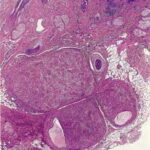

Atlas of skin histopathology

Nodular hidradenoma =الغدوم العرقي العقيدي